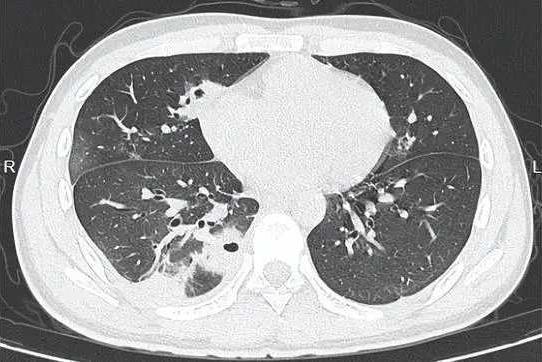

熬到第三天,小林体温飙至39℃,赶紧就医。CT检查结果让医生都皱眉:他的肺里布满了十几个空洞,部分肺组织已经坏死,确诊为血源性肺脓肿!细菌培养显示,罪魁祸首是“金黄色葡萄球菌”——这种藏在每个人皮肤表面的细菌,竟顺着挤痘的伤口闯进了血液,一路侵袭到肺部。